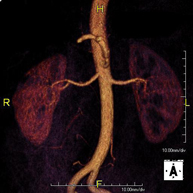

Prueba diagnóstica no invasiva que consiste en la obtención de imágenes de alta definición anatómica de todo el cuerpo mediante el empleo de un campo electromagnético y ondas de radio (con un emisor y un receptor). No utiliza radiación ionizante. Es una prueba muy importante en la búsqueda de metástasis en pacientes con neoplasia conocida. No requiere preparación previa. No es necesario el empleo de contraste paramagnético (Gadolinio). - Angio-RM Aorta abdominal

Prueba diagnóstica no invasiva que consiste en el estudio de la arteria aorta abdominal, obteniendo imágenes de alta definición anatómica mediante el empleo de un campo electromagnético y ondas de radio (con un emisor y un receptor). Es indispensable el uso de contraste paramagnético (Gadolinio). Sin embargo, no utiliza radiación ionizante. La calidad de las imágenes permite realizar reconstrucciones en 2D y 3D. Está indicado en aquellos pacientes con enfermedad vascular (aterosclerosis), estudio de aneurismas, en estudios pre-quirúrgicos de lesiones adyacentes a la aorta abdominal como "mapa" vascular, etc. - Angio RM Aorta-ilíaca

Prueba diagnóstica no invasiva que consiste en el estudio de la arteria aorta abdominal de las arterias ilíacas, obteniendo imágenes de alta definición anatómica mediante el empleo de un campo electromagnético y ondas de radio (con un emisor y un receptor). Es indispensable el uso de contraste paramagnético (Gadolinio). Sin embargo, no utiliza radiación ionizante. La calidad de las imágenes permite realizar reconstrucciones en 2D y 3D. Esta prueba está especialmente indicada como estudio pre-quirúrgico (mapa vascular) antes de intervenciones percutáneas o quirúrgicas de aorta abdominal y arterias ilíacas, estudio complementario en pacientes con isquemia de miembros inferiores, etc. - Angio RM Arterial extremidades inferiores

Prueba diagnóstica no invasiva que consiste en el estudio de la arteria aorta abdominal, obteniendo imágenes de alta definición anatómica mediante el empleo de un campo electromagnético y ondas de radio (con un emisor y un receptor). Es indispensable el uso de contraste intravenoso paramagnético (gadolinio). Sin embargo, no utiliza radiación ionizante. La calidad de las imágenes permite realizar reconstrucciones en 2D y 3D. Está indicado en aquellos pacientes con enfermedad vascular (aterosclerosis), estudio de aneurismas, en estudios pre-quirúrgicos de lesiones adyacentes a la aorta abdominal como "mapa" vascular… - Angio-RM Aorta iliaca

Prueba diagnóstica no invasiva que consiste en el estudio de la arteria aorta abdominal, obteniendo imágenes de alta definición anatómica mediante el empleo de un campo electromagnético y ondas de radio (con un emisor y un receptor). Es indispensable el uso de contraste intravenoso paramagnético (gadolinio). Sin embargo, no utiliza radiación ionizante. La calidad de las imágenes permite realizar reconstrucciones en 2D y 3D. Esta prueba está especialmente indicada como estudio pre-quirúrgico (mapa vascular) antes de intervenciones percutáneas o quirúrgicas de aorta abdominal, estudio complementario en pacientes con isquemia de miembros inferiores… - Angio-RM Arterias renales